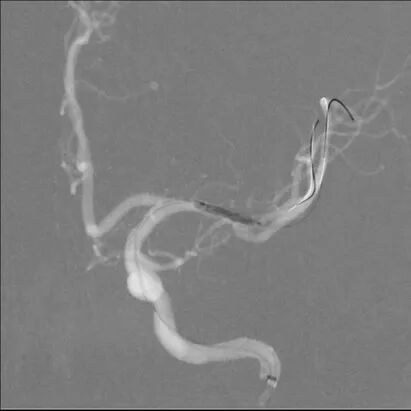

在大脑中动脉M1末端及上干起始段置入赛诺神畅 颅内药物支架NOVA DES®2.25*10mm,球囊扩张成形,支架成形好,狭窄处扩张好,下干未闭塞。

支架释放

全脑及病变处不同体位造影:狭窄处成形好,未残余明显狭窄,左大脑中动脉主干及各分支显影好。

术中将Navien导管送至颈内动脉岩骨段,增加支撑力,将两条微导丝分别送入左大脑中动脉上下干,先沿上干微导丝送入球囊扩张,效果差, 再沿下干微导丝送入球囊扩张,效果仍差,大脑中动脉M1末端狭窄有改善,但狭窄仍较重,遂用赛诺神畅 颅内药物支架NOVA DES®2.25*10mm置入左大脑中动脉M1末端及上干内,球囊扩张成形,支架成形好,血管成形满意,确定下干无闭塞后,撤出下干微导丝。